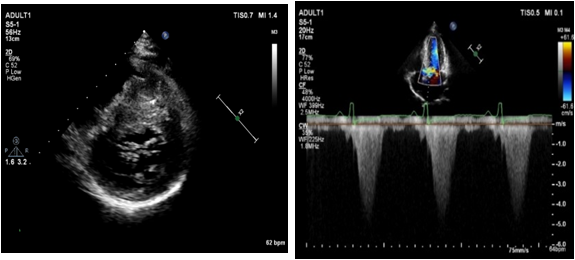

Liwen术式病例介绍

|作者:李静 刘丽文

|单位:空军(第四)军医大学西京医院